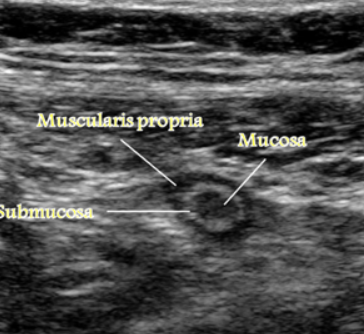

Longitudinal GI tract

Trans GI tract